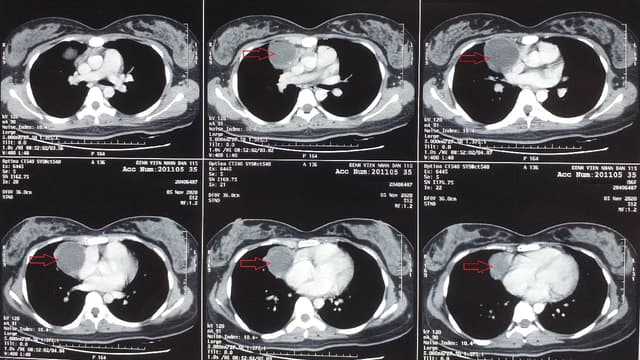

Thu Cúc TCI tặng 35% phí chụp CT phổi giúp khám phổi hiệu quả

Hút thuốc lâu năm và các tác hại từ ô nhiễm môi trường… là những con đường dẫn thẳng đến bệnh phổi. Có rất nhiều biến chứng nghiêm trọng do bệnh về phổi, thậm chí đe dọa tính mạng. Vì vậy, việc thăm khám, rà soát và phát hiện sớm, ngăn kịp thời các bất […]